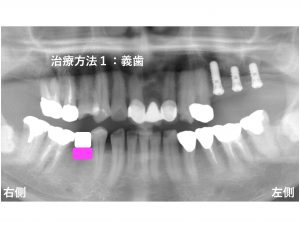

以下が初診時です。

多くの歯が欠損しています。

上顎左側が3歯欠損、

上顎右側が1歯欠損、

下顎右側が1歯欠損

しています。

この欠損部位の治療の選択肢としては、

3つの治療法が考えられます。

一つ目は、義歯(入れ歯)です。

患者様は、義歯はご希望されませんでした。

二つ目は、ブリッジです。

患者様は、今まで多くの歯を削ってきた経験から

できるかぎり歯を削りたくないとのご希望がありました。

次の治療プランは、インプラントです。

患者様は、インプラント治療をご希望されました。